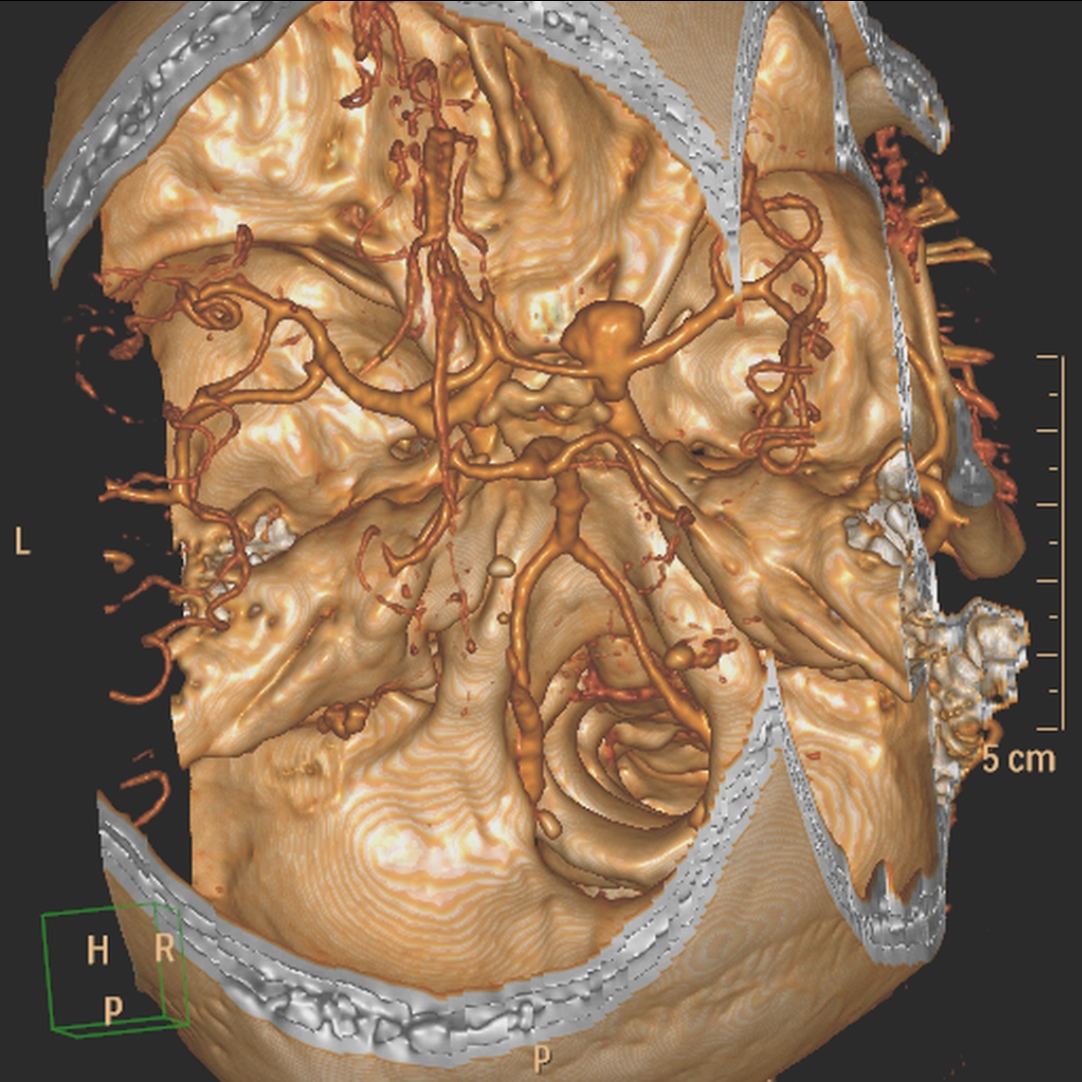

Se decide realizar Angio-TC.

Angiografía- TC: Se basa en la TC de cortes helicoidales. Aunque implica radiación para el paciente y requiere administración de contraste iodado intra-venoso (no requiere cateterización arterial), el hecho de que posea gran disponibilidad y sea una técnica rápida y fácil de llevar a cabo en pacientes enfermos, hace que se use como prueba de primera línea. Se puede realizar con cortes de 1 mm y realizaremos reconstrucciones para obtener imágenes como las de una angiografía (cine + MIP).